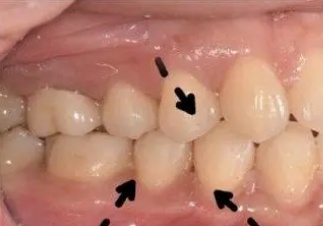

“楔状缺损”是牙齿颈部经过缓慢磨耗而形成的缺损,呈“V”状,由于它外形酷似木匠用的楔子,因此称为“楔状缺损”。多见于前牙或双尖牙的唇面,以中老年患者居多。

楔状缺损较浅时可无症状,较深时可表现为冷、热刺激痛,随病情发展还可出现自发痛,也有些患者由于进程缓慢、痛阈较高,可直至露髓而无明显痛觉。

楔状缺损还可伴有牙龈退缩,并可引起牙髓病、尖周病,严重者可导致牙冠折断。

临床上看,牙颈部楔状缺损更多是位于上下颌口角区域的牙齿,这是因为这些牙处于牙列拐角处,刷牙时受到的力也是最大的。